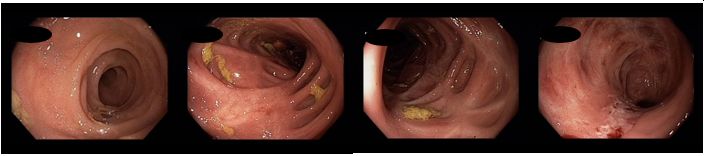

Koloskopie 2022/2: Pozánětlivé změny celého tračníku (jizvy), v rektosigmatu je reziduální ulcerace v centru serpiginózní ulcerace – bez makroskopických známek aktivity v tračníku i terminálním ileu. Vyšetření v bílém světle i NBI

Histologie: Chronické a fokálně výrazně aktivní zánětlivé změny v materiálu číslo IV., kde nález připouští diagnózu idiopatického střevního zánětu charakteru Crohnovy choroby s aktivitou